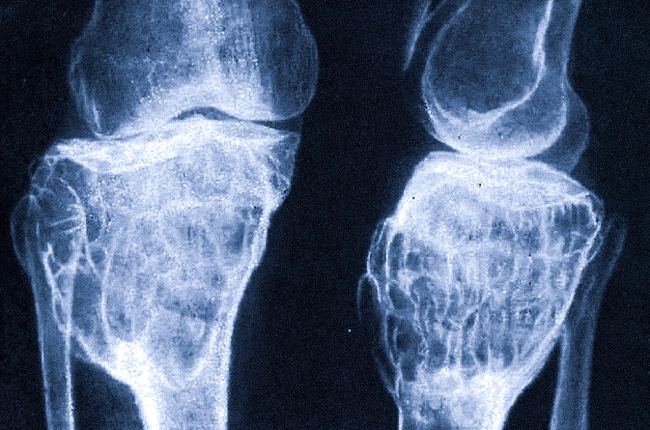

Когда мы говорим о здоровье стопы, часто упускаем из виду важные клеточки, которые играют критическую роль в поддержании её структуры и функции. Остеобласты и остеокласты, два типа клеток, которые непосредственно контролируют процесс формирования и разрушения костной ткани. Эти клетки работают совместно, чтобы поддерживать баланс в нашем организме, и их работа в стопе имеет свои уникальные особенности.

Остеобласты — это клетки, отвечающие за образование костной ткани. Имея форму многоугольников, они синтезируют и вырабатывают матрикс костной ткани, а также регулируют минерализацию, которая необходима для крепости кости. Эти клетки активно участвуют в процессе костеобразования и восстановления тканей после травм.

С другой стороны, остеокласты выполняют противоположную функцию. Это крупные многоядерные клетки, которые ответственны за резорбцию кости — процесс разрушения костной ткани. Они очень важны для поддержания нормального функционирования скелета, так как помогают регулировать уровень кальция и фосфора в организме.

Минерализация — это процесс, в котором остеобласты вырабатывают коллаген и ненасыщенные карбонаты, что в совокупности с кальцием приводит к постепенному образованию жесткой кости. Это критически важно для стопы, так как наличие крепкой костной структуры предотвращает возможные травмы и деформации.

Остеопороз — это одно из самых распространенных заболеваний, касающихся остеобластов и остеокластов. При этом заболевании баланс между образованием и разрушением костной ткани нарушается, что приводит к потере костного вещества и увеличению хрупкости костей. Стопа, будучи самой нижней частью тела, часто оказывается подверженной этому состоянию.